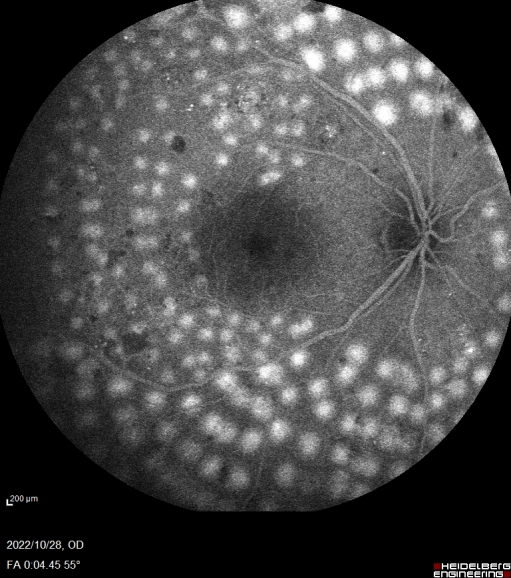

眼底血管造影是眼科临床上非常重要的检查方式,广泛应用于眼底血管疾病。海德堡共焦激光同步血管造影系统采用独特的共焦激光造影,只接受共焦平面的发射光,没有散射光干扰,可以获得高分辨率、高对比度的造影图像。同时基于共焦激光逐点扫描的特点和激光的高准直性,Spectralis HRA在小瞳下也可以获取高质量图像。可以同步进行FFA和ICGA造影,一次拍摄可将视网膜与脉络膜的血管造影实时同屏显示,方便临床医生进行同步对比观察,为诊断提供更全面和精准的信息。

此次合肥普瑞眼科医院引入的海德堡 Spectralis HRA共焦激光同步血管造影系统可配备有“天幕”102°超广角镜头,是造影设备的全新升级。102°超广角造影图像的观察范围更广,有效涵盖周边眼底,可以更早的发现早期糖尿病视网膜及一些血管性疾病的周边部改变,对于控制患者病情发展,减少视力损害意义重大。同时Spectralis HRA还具有动态造影的独特功能,每秒钟可以获取16帧高清图像,全程记录血管充盈过程,不遗漏重要细节。

10月28日,眼底病专科副主任张思伟利用海德堡 Spectralis HRA共焦激光同步血管造影系统顺利完成首例患者广角眼底血管荧光造影检查,为眼底病患者后续相关治疗提供有力支持,标志着合肥普瑞眼科医院眼底病专科诊疗水平再上新台阶。未来,合肥普瑞眼科医院将始终秉承“用爱传递光明”的理念,坚持以患者为中心,优化医院重点特色专科建设,全面提升医院各项诊疗服务水平,为人民群众的眼健康保驾护航!